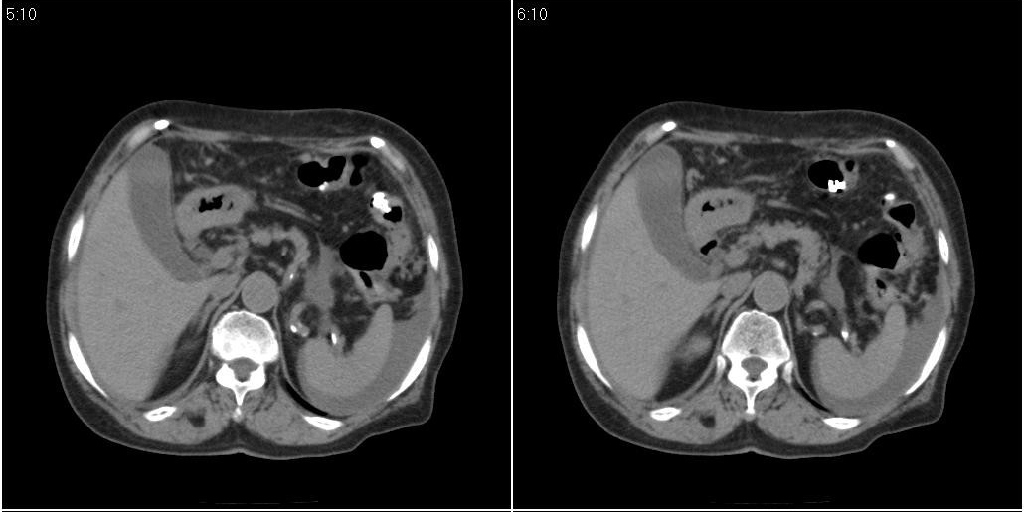

胆囊有问题么,是结石么?胆囊内异常密度平扫30hu左右,增强各期无变化。

支持!另腹腔少量积液。

胆囊炎,胆结石,胆囊窝积液,胸腹水。

胆囊内稍高密度影,无强化,胆囊壁增厚,周围见低密度影,右侧膈肌角及脾周水样密度,支持胆囊泥沙样结石,胆囊炎、胆囊窝积液,胸腹水。